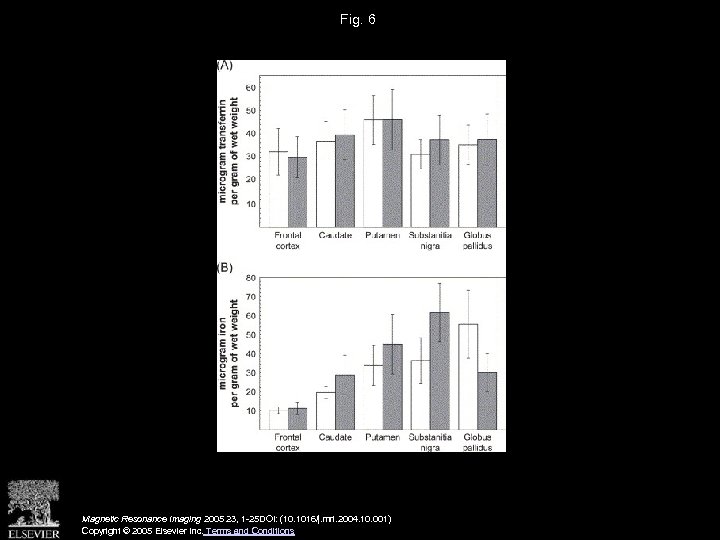

Fig. 6 Magnetic Resonance Imaging 2005 23, 1 -25 DOI: (10. 1016/j. mri. 2004. 10. 001) Copyright © 2005 Elsevier Inc. Terms and Conditions